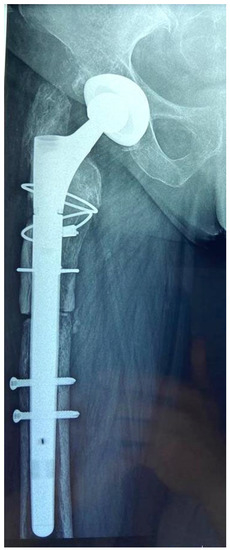

The length of the osteotomized bone fragment (OBF) is essential; it must be long enough to allow the easy removal of the stem with or without cement but without affecting the primary stability of the revision stem. Accurate preoperative planning is very important for this reason. On the right magnification A-P and profile hip X-rays, we measured the length of the stem and the length of the distal cement plug including the length of the plastic restrictor, taking the tip of the greater trochanter as a reference point. For cementless stems, it is not necessary for the OBF to reach the level of the stem tip, only up to approximately 2 cm, whenever it is preoperatively intact (Figure 1). Maintaining the integrity of at least the femoral isthmus is mandatory. Usually, the length of the OBF is 15–16 cm. A varus remodeling aspect can be corrected by adding the osteotomy of the internal cortex (Figure 2).

Figure 1. Maintaining the integrity of the femoral isthmus is mandatory; a minimal contact of 2 cm is necessary for primary stability of the stem.